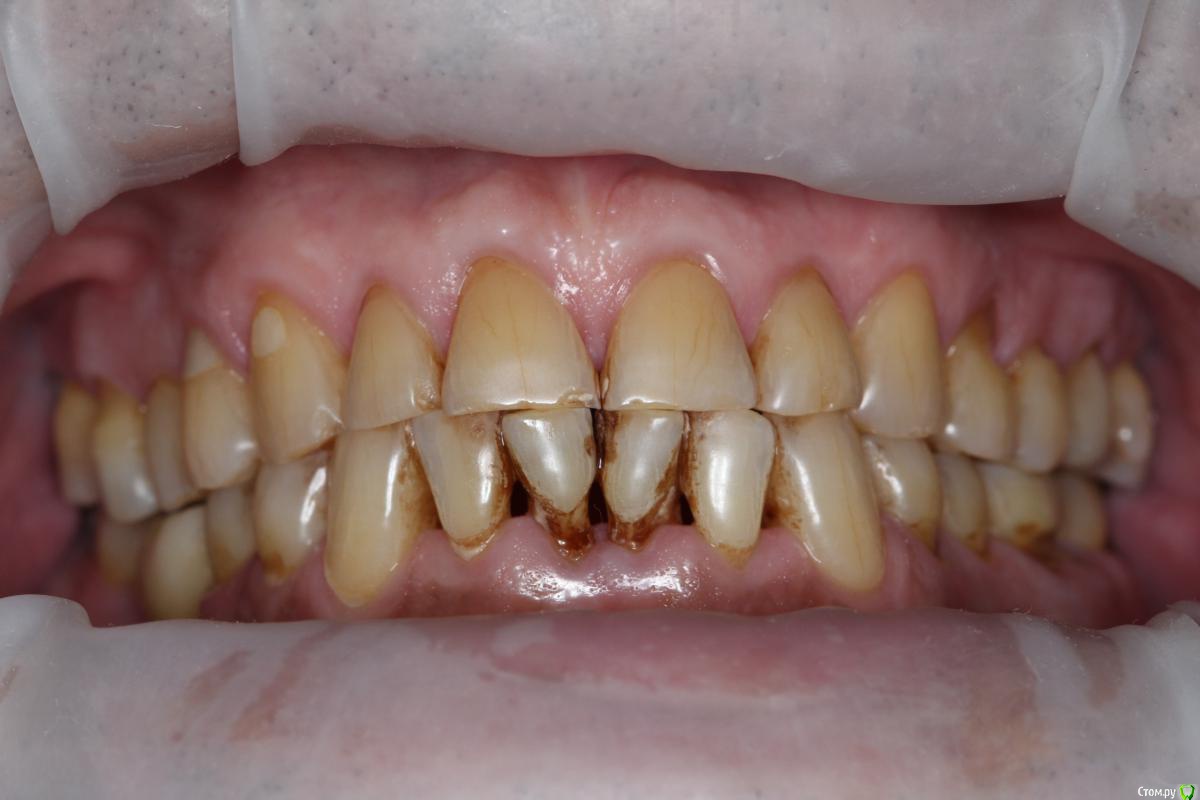

Robinbobin Опубликовано 27 марта, 2015 Поделиться Опубликовано 27 марта, 2015 (изменено) Пациент 57 лет с жалобами на стираемость зубов,чувствительность и бруксизм Хотелось бы услышать ваше мнение!!!! Изменено 27 марта, 2015 пользователем Robinbobin Ссылка на комментарий

Robinbobin Опубликовано 28 марта, 2015 Автор Поделиться Опубликовано 28 марта, 2015 а с чем к вам этот пациент пришел с какой проблемой?С жалобами на стираемость,чувствительность зубов!!! Ссылка на комментарий